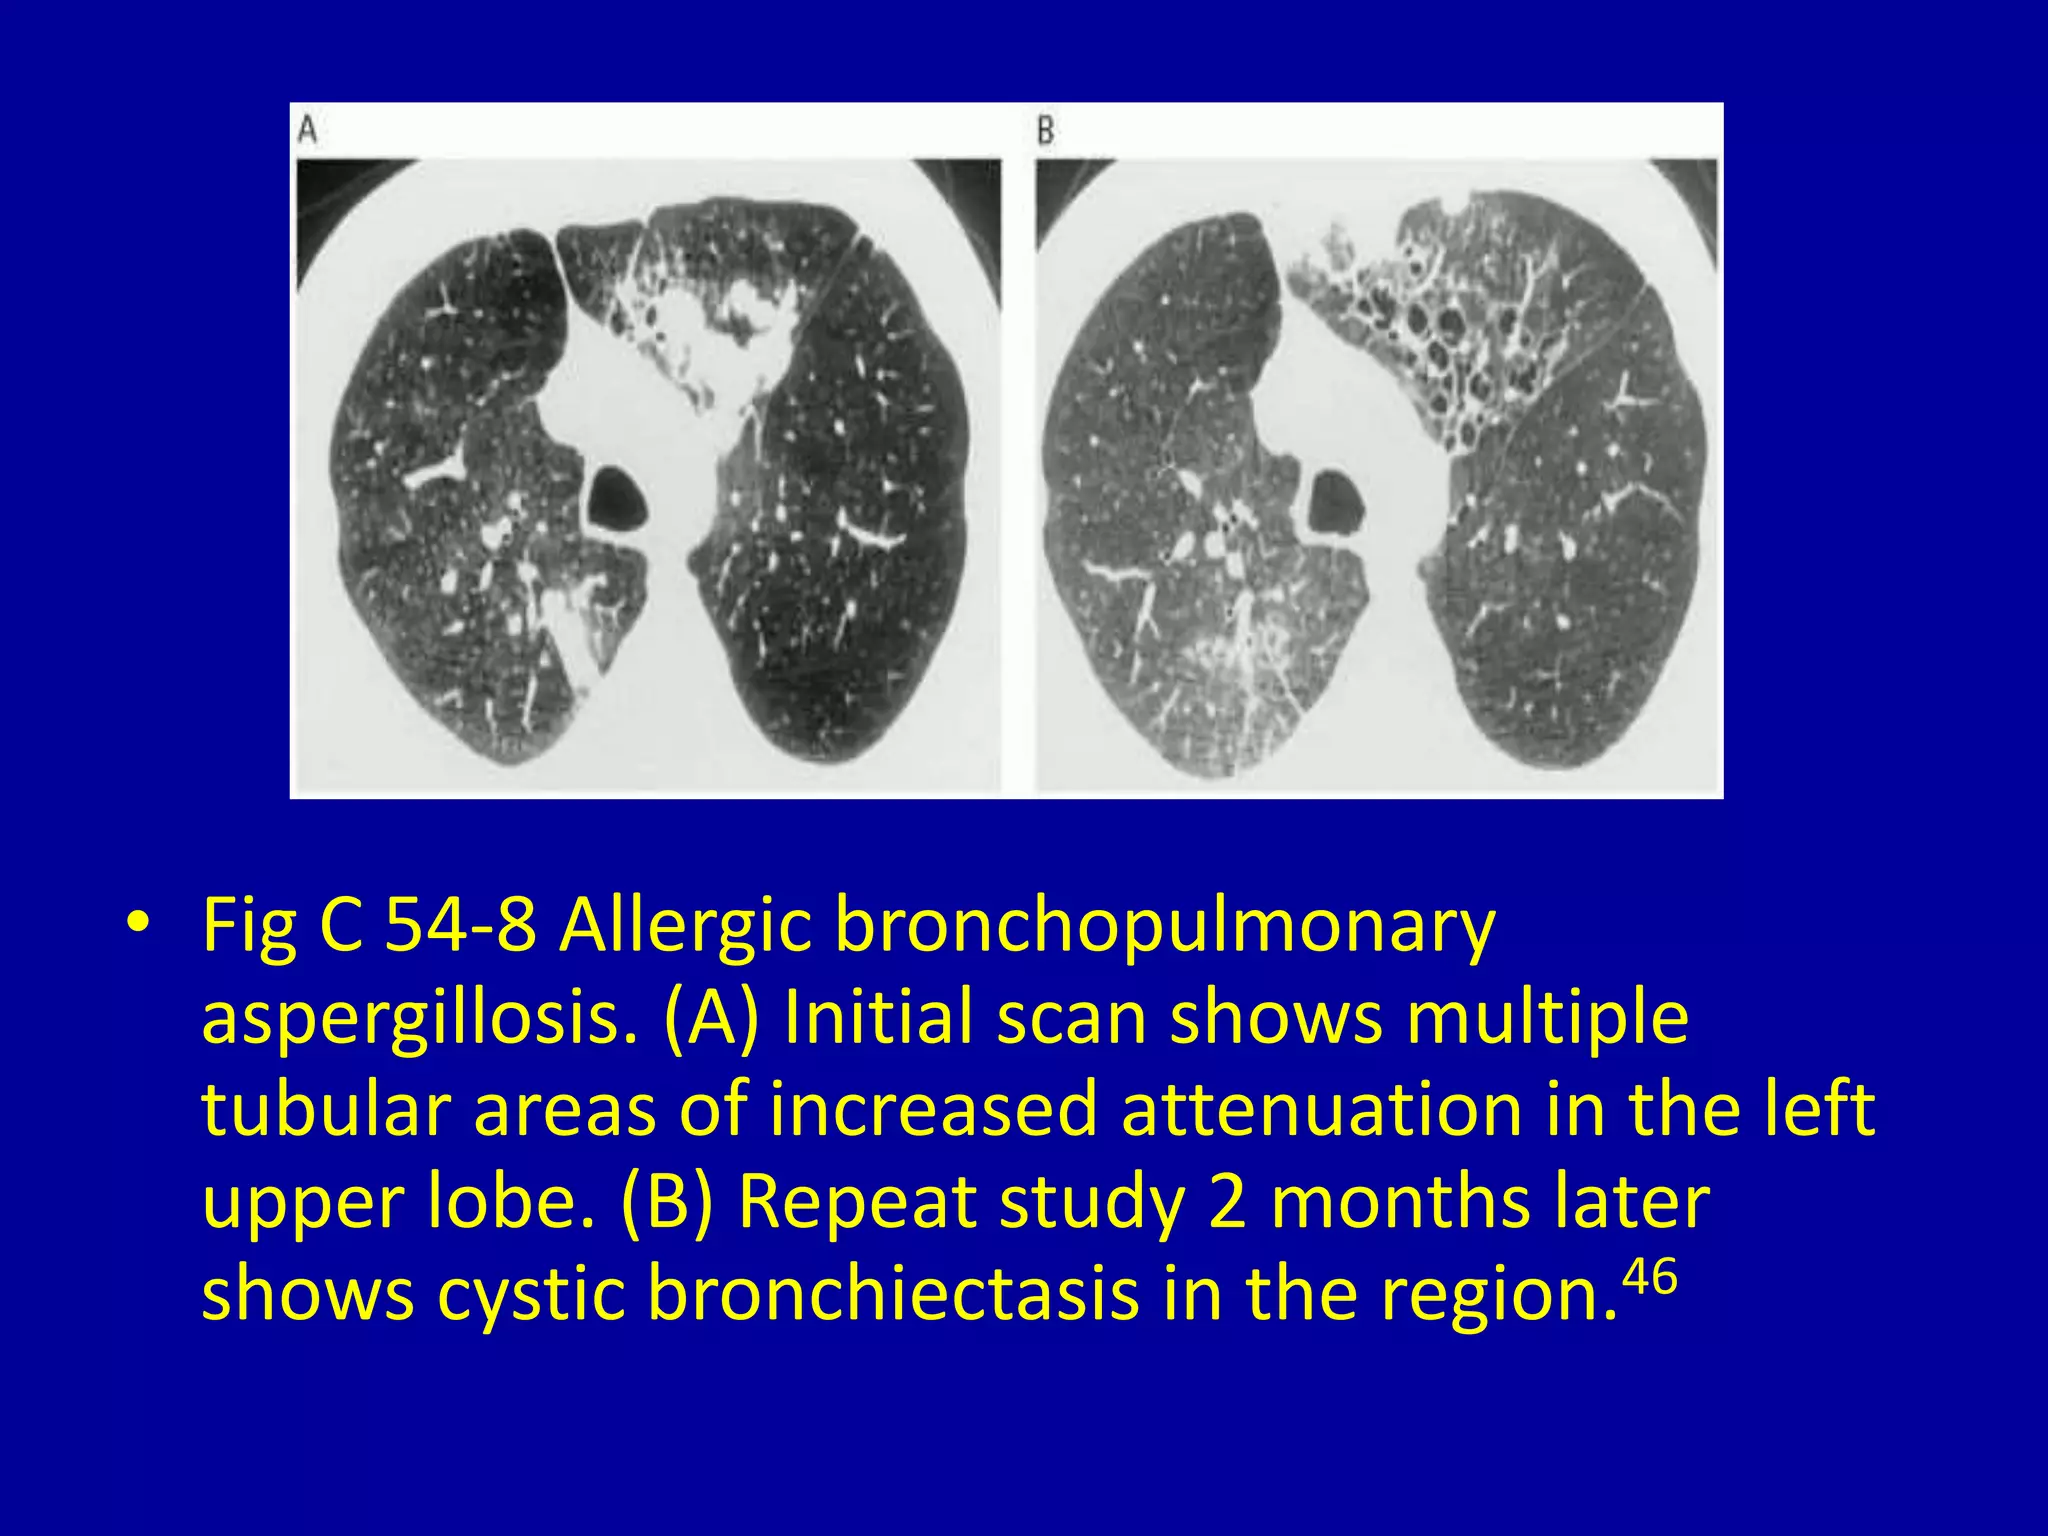

This document discusses various pulmonary diseases that predominantly affect the upper zones of the lungs. It includes 10 figures showing CT scan findings of different conditions like postprimary tuberculosis, sarcoidosis, pulmonary Langerhans cell histiocytosis, silicosis, centrilobular emphysema, chronic eosinophilic pneumonia, cystic fibrosis, allergic bronchopulmonary aspergillosis, neurogenic pulmonary edema, and ankylosing spondylitis. The images demonstrate lesions, nodules, consolidations, cysts, and other abnormalities that are largely limited to the upper lobes and regions of the lungs.